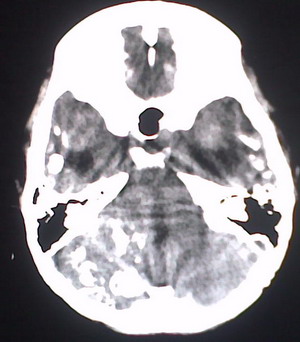

以下是引用jiajie在2009-2-3 20:02:00的发言:[br]脑室周围白质区可见大量斑片状钙化,部分融合成带状,双侧侧脑室及第三脑室扩大。[br]考虑弓形体原虫感染。(先天性宫内感染、torch综合症)

以下是引用lkc8963在2009-2-3 21:15:00的发言:[br]临床眼睑可见静脉扩张,ct双侧眼上静脉亦示扩张,颅内钙化以皮层\\软脑膜为主而不是位于白质和室管膜,再加上静脉窦异常,还是应该考虑静脉血管瘤病,可能为较复杂的血管畸形.

以下是引用卜一在2009-2-4 9:21:00的发言:[br]sturge-weber综合征:面部三叉神经分布区的毛细血管性或海绵状血管瘤以及同侧枕、顶或额叶软脑膜的血管瘤(以静脉性为主)。脑皮质,特别是第二三层,毛细血管可有增厚和钙化。局部发生层状坏死、神经细胞脱失、萎缩、胶质细胞增生及钙盐沉着。可根据面部典型分布的特征性皮痣作出诊断。头颅ct:发现面部血管瘤同侧的脑内病理钙化影,呈双层线条波浪形、脑回形或树枝形。本例支持:sturge-weber综合征![br]